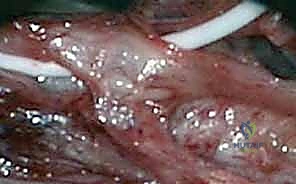

في هذه العملية، يقوم الجراح بفتح المنطقة المصابة والوصول إلى العصب. يجد الجراح أن العصب محاط بأنسجة ليفية وندبات خارجية تعصره وتضغط عليه.

* الخطوات: يتم تحرير العصب بدقة متناهية من الأنسجة المحيطة به على طول منطقة الإصابة حتى يعود للعصب لونه الطبيعي ويتحرر من أي ضغط.

* الهدف: استعادة التروية الدموية للعصب وإزالة الضغط الميكانيكي.

ثانياً: عملية تحرير العصب الداخلي (Internal Neurolysis)

إذا كان العصب بعد تحريره من الخارج لا يزال يبدو متصلباً أو منتفخاً (Neuroma in continuity)، فهذا يعني أن التليف موجود داخل العصب نفسه، بين الحزم العصبية.

* الخطوات: باستخدام الميكروسكوب الجراحي، يقوم أ.د. محمد هطيف بفتح غلاف العصب الخارجي (Epineurium) بلطف شديد، ثم يقوم بتسليك وتحرير الحزم العصبية (Fascicles) الفردية من النسيج الندبي الداخلي.

* الخطورة: هذه الخطوة دقيقة جداً وتحتاج ليد خبيرة، لأن أي خطأ قد يؤدي إلى قطع الحزم العصبية السليمة.